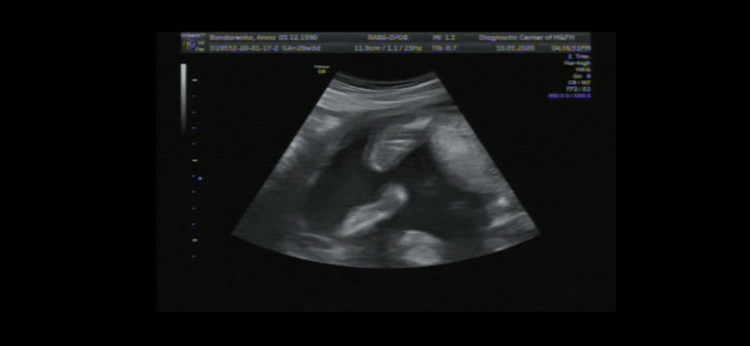

Как мой сын пинал меня на УЗИ 😄

Ннна тебе, мама, с обеих ног))) со вчерашнего второго скрининга, вот так выглядят пиночки 🤗